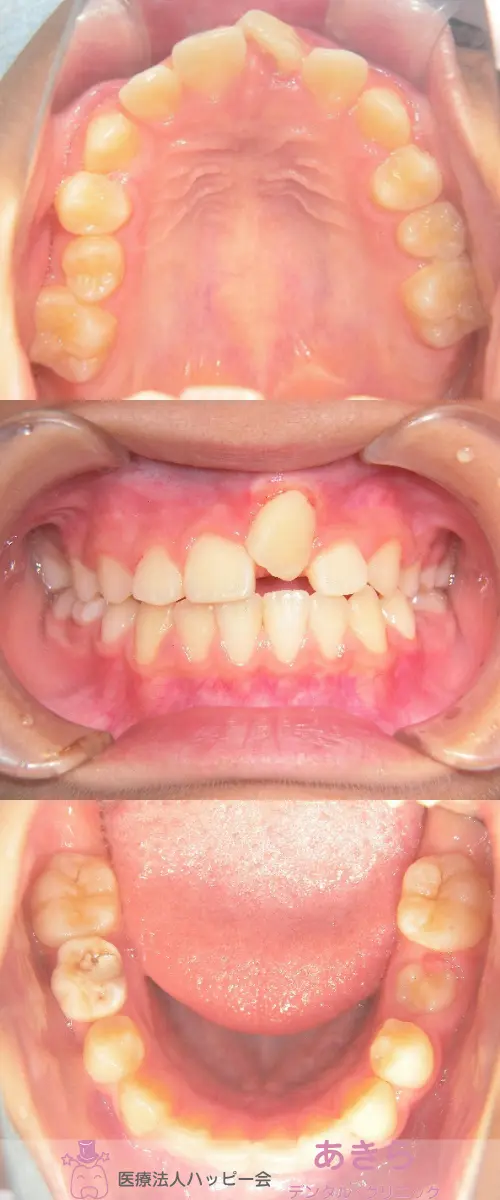

2019年10月6日 口腔内写真

2019年11月29日 口腔内写真(SH装置スタート)